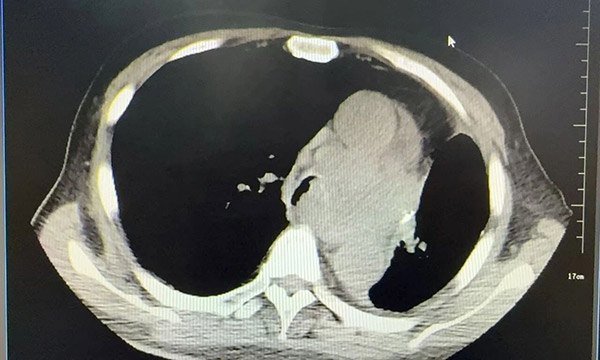

胸部CT:

患者张某,男性,75 岁,既往因肺腺癌接受左肺部分切除术。然而术后两年,他却因左总支气管肿瘤复发,再次陷入呼吸困难的险境,不除外化疗相关间质性肺疾病,入住医院呼吸与危重症医学科五病区。影像与内镜显示,肿瘤几乎完全堵塞主支气管,随时可能出现窒息风险。